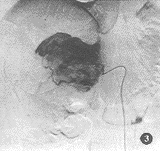

腹主动脉造影显示右侧肾上腺区少许肿瘤血管染色。选择性肾上腺动脉造影显示动脉期右肾上腺动脉不同程度增粗,肿瘤血管多而密集,呈网状,走行纡曲,粗细不均,以肾上腺中动脉造影时更明显。2例见少许静脉早显。实质期肿瘤染色浓密,不均匀。静脉期仍可见肿瘤较长时间淡薄染色(图1~3)。2例在血管造影中血压突然升高,达200~250/120~140 mmHg,伴恶心、腹痛,经降血压,镇痛等对症处理后,症状缓解。

图3 导管位置同图2,造影显示静脉期见肿瘤持续染色,并见少血管区